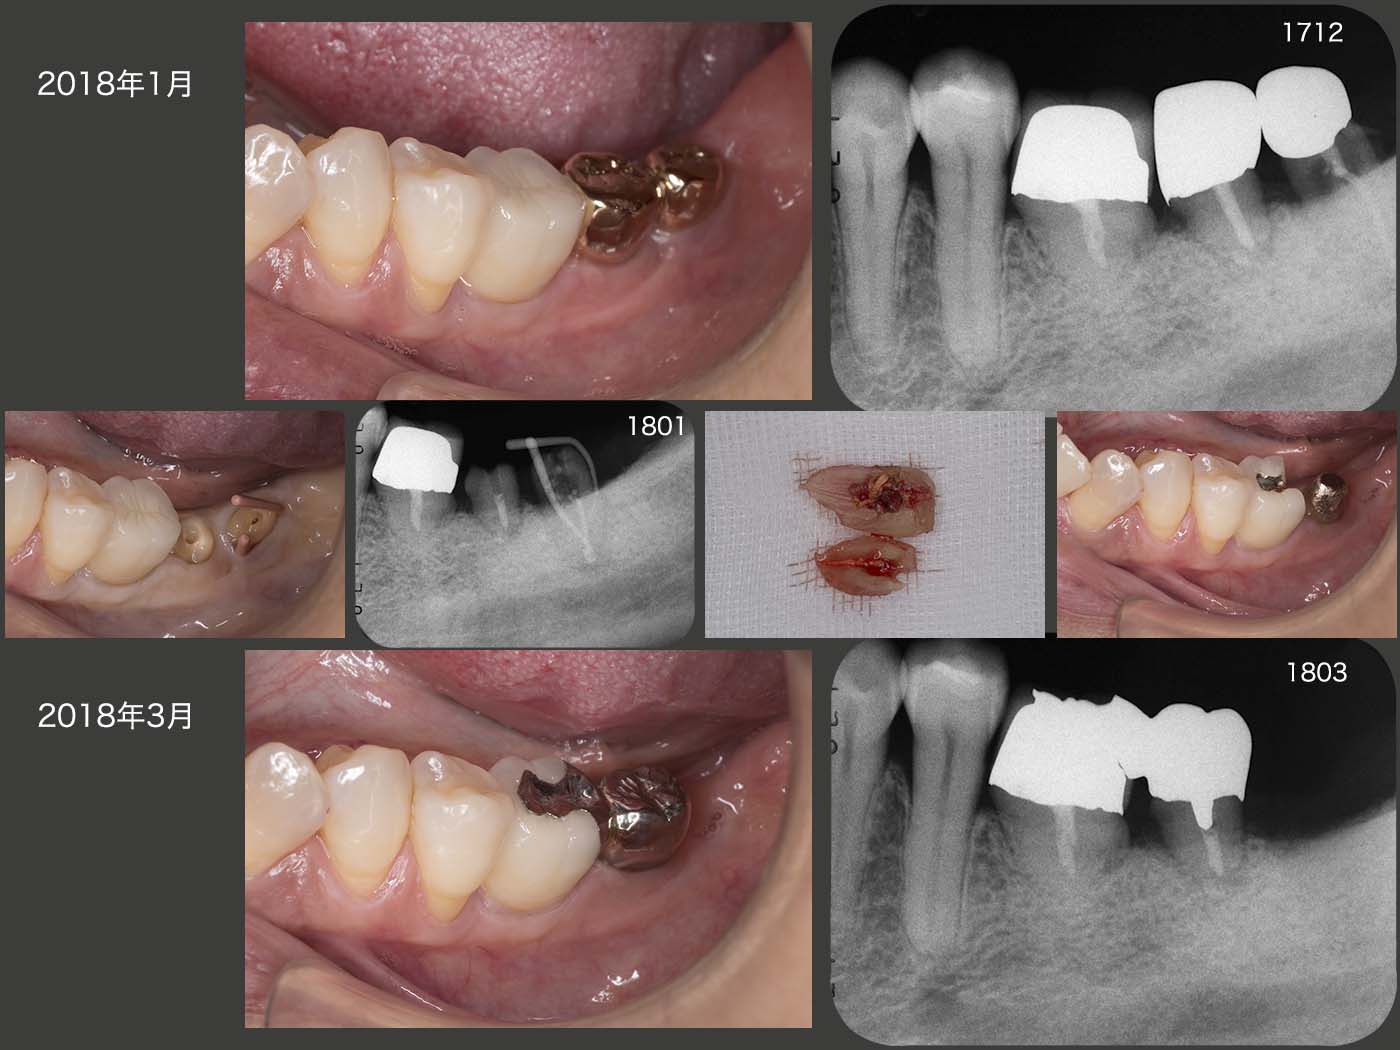

2017年12月,左下3本の移植歯の内,一番後方歯の歯周ポケットが急に最大9mmの値を示した.デンタルX線写真を撮影したところ歯根破折らしき像が認められた.特に症状がなかったので,18年1月,正月明けに精査したところ,保存は無理であると判断し抜去した.やはり歯根破折していた.手前の移植歯は,歯周ポケットは3mm以下であったが,著しく動揺していた.初診終了から約10年経っているが,ここまで左側の奥で咀嚼しているとは想像できなかった.結果的に判断すれば,移植した3本を連結固定したほうが良かったかもしれない.

本来は移植歯の一番前方歯のメタルボンド冠を外して,後方歯と連結固定するべきであるが,今回はメタルボンド冠にインレー形成を行い,後方歯と連結固定した.(インレーの近心部にピンを形成し,保持を増強した.)今後経過を観察し,問題があれば再度作り直すつもりである.